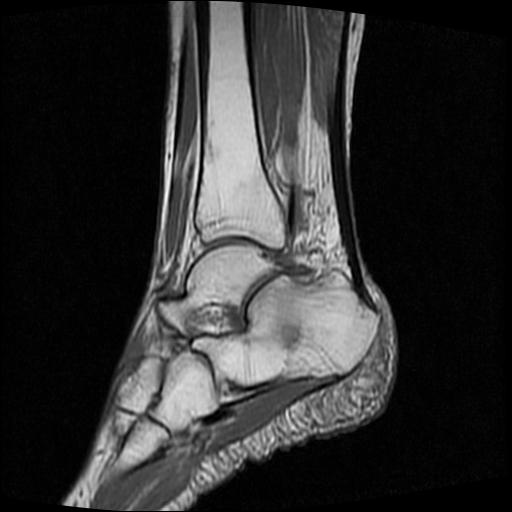

女性,70岁,右侧跟骨疼痛2个月,负重时加剧,不负重时不疼。

胫骨下段,跟骨、距骨可见斑片状异常信号区;考虑:转移瘤

跟骨长t1长t2信号异常,边缘模糊(肿瘤一般边界清楚,故肿瘤不考虑),压脂像呈高信号--骨髓水肿(炎症?)。